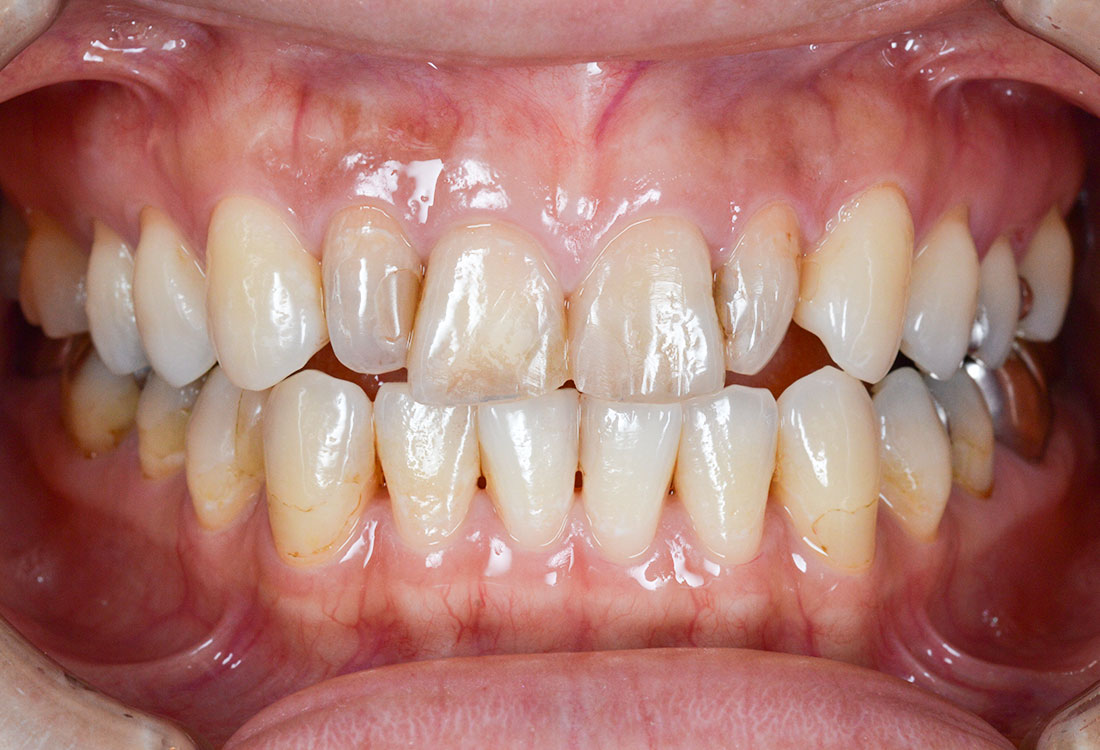

治療症例 Case3

Treatment cases

ご相談内容

- 上の左右2番目の歯と尖っている前歯が気になる

- 歯の形を治したい

- 歯の色をきれいにしたい

ホワイトニングで全体的に白くした後、その色に合わせて被せ物を作っていきます。

治療内容

模型を作成して最終的な形を模索します。

ファイバーコアで神経のない歯に土台を作ります。

ファイバーコアは保険治療で使われるメタルコアと異なり白く、被せ物が透けて黒く見えません。

土台になる歯の形を整えて最終的な形の模型を作ります。

治療後

白く明るい口元になりました。